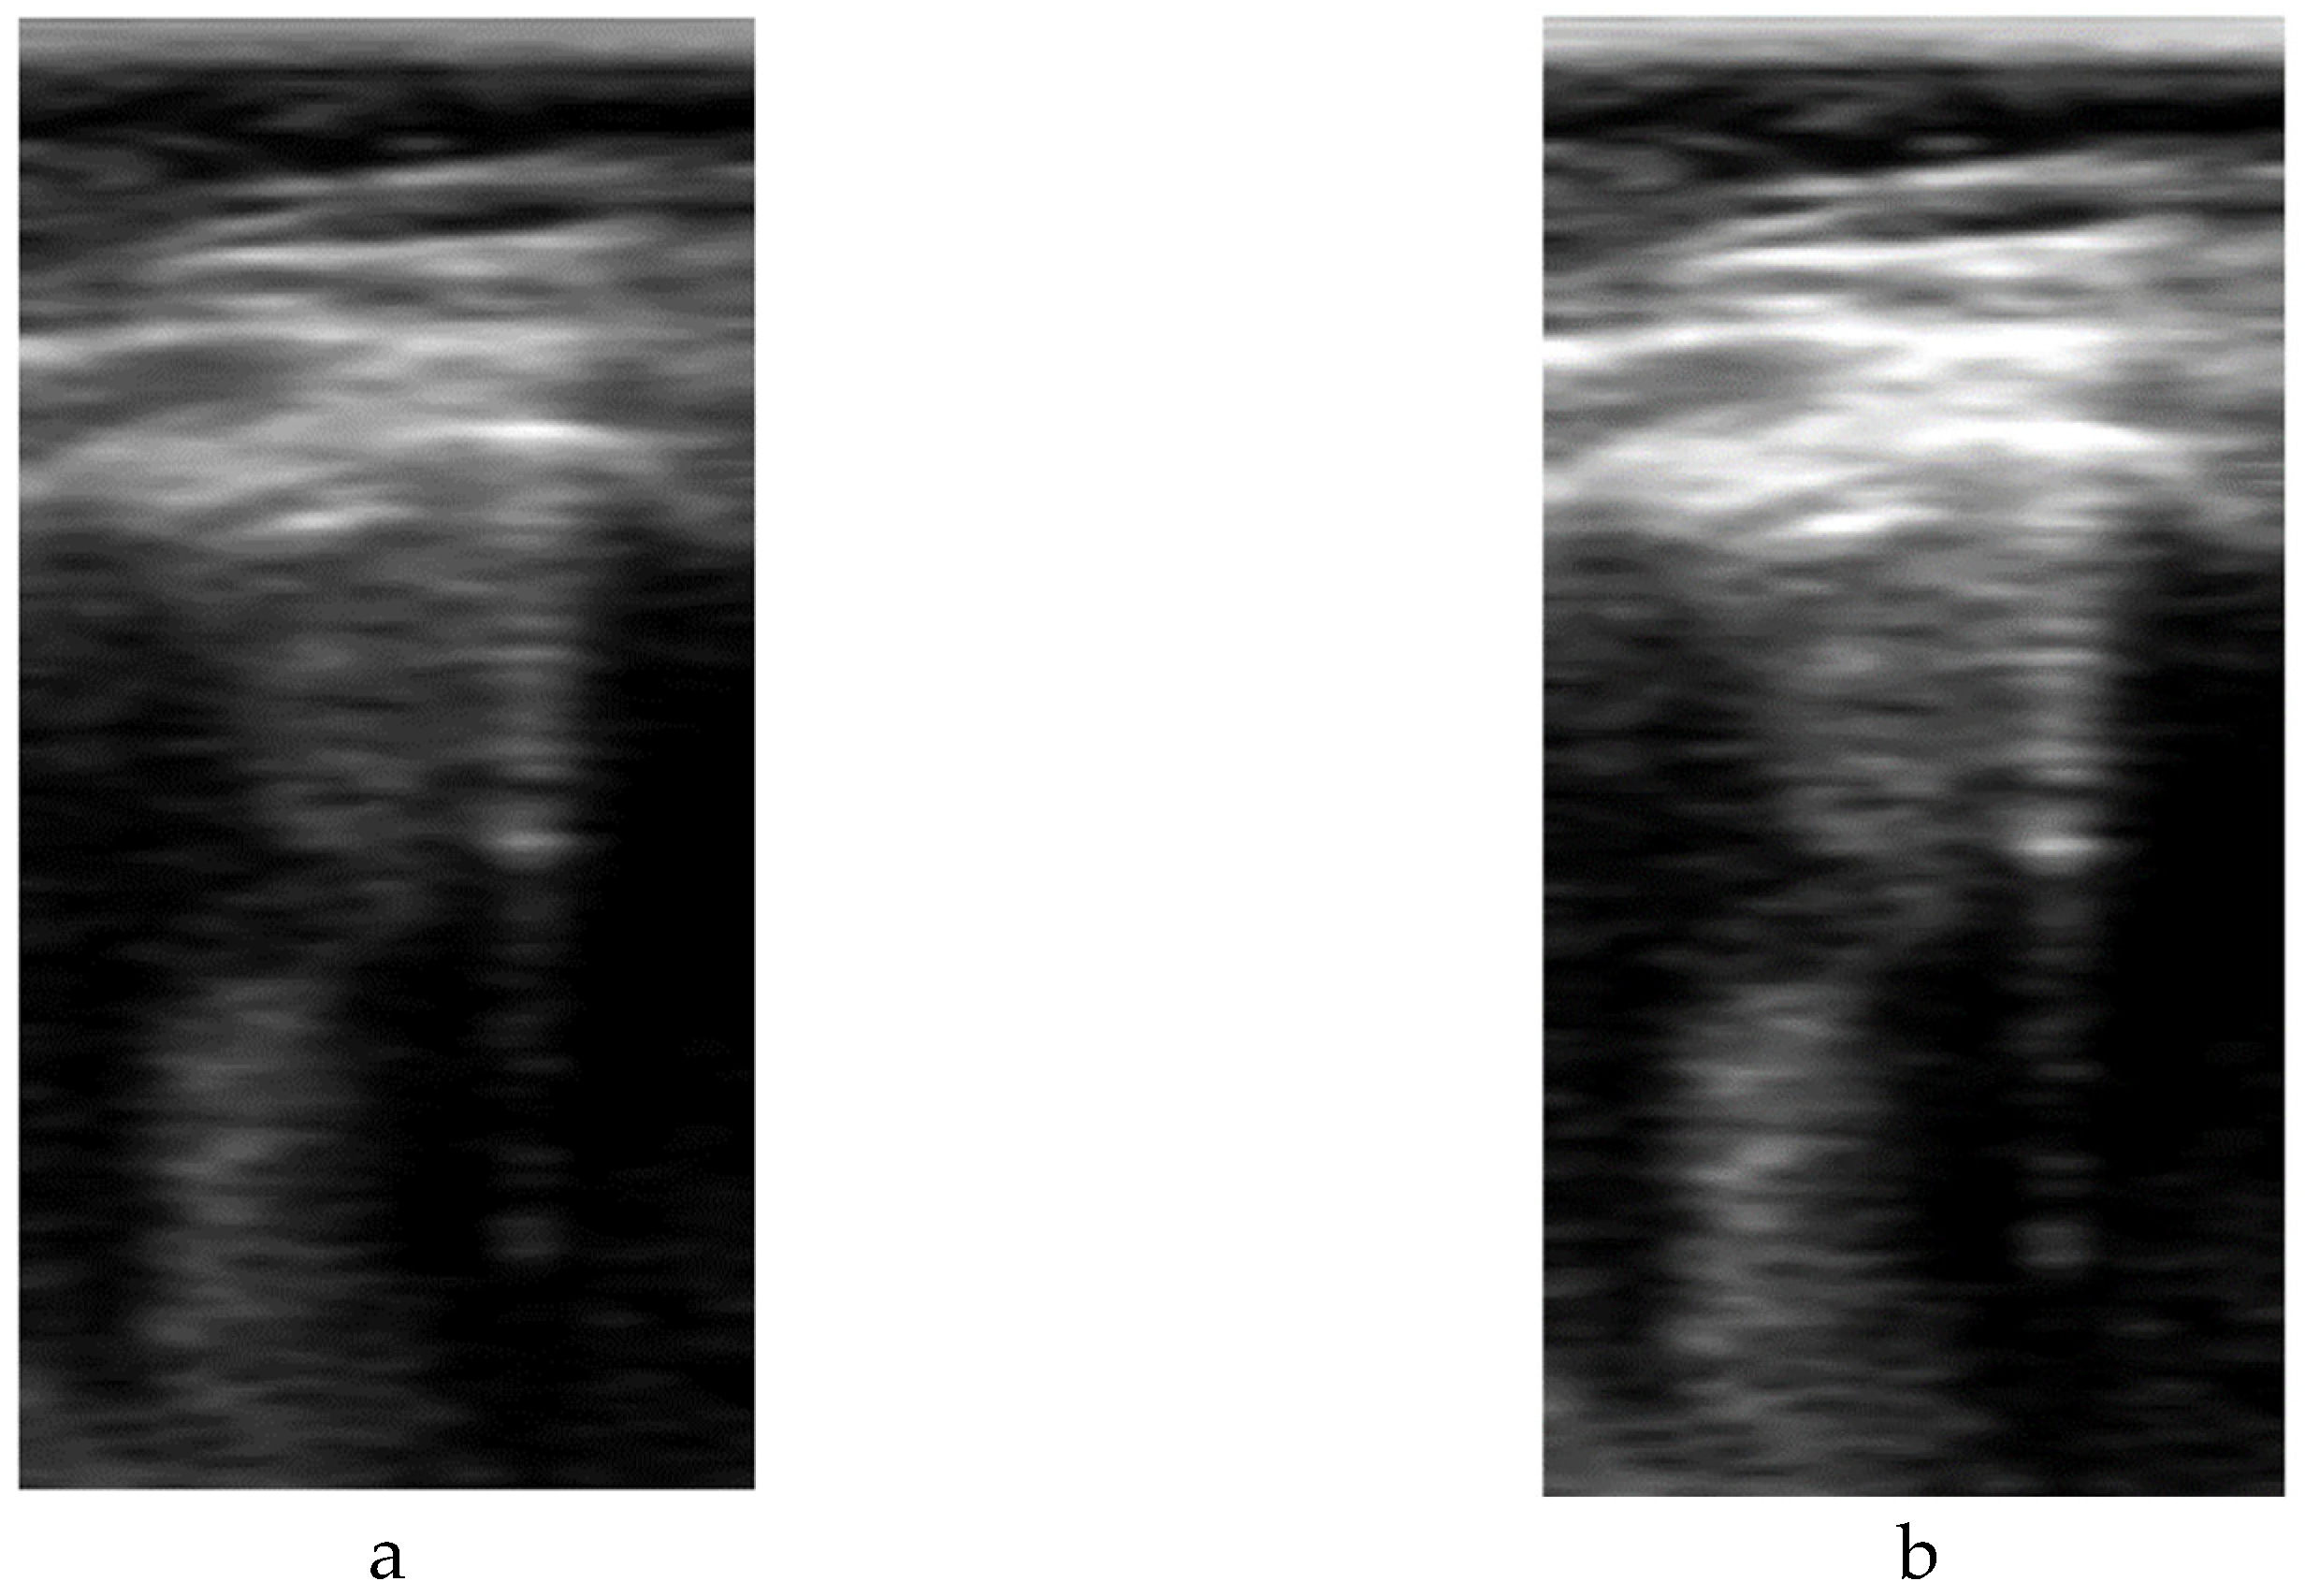

Figure 3. Comparison between sectorial image (a) and B-Scan (b).

The size of the vertical direction is related to the frequency content of the signal and the sampling rate. For an ideal 100% bandwidth array, the maximum frequency content of the signal envelope is equal to half the array center frequency. To reconstruct the envelope without aliasing, the pixel density in the vertical direction should be, at least, able to sample the signal at double of that frequency (Nyquist criteria). For the array used in this work with 3.5 MHz center frequency and 70% bandwidth, the number of pixels required for sampling up to 70 mm and 90 mm is 210 and 294 respectively. Based on these numbers, a height of 256 was selected for the network, which imposes a trade-off between training and inference cost and image quality. In case that larger images are used, they should be scaled down using compression algorithms that preserve the artifacts information. For example, in the scanner used in this work, a data reduction algorithm without peak information losses is available [22], and was used to accommodate the B-Scan height to the network size. In Figure 3, a comparison example between sectorial and B-scan images is shown.

The format of the input data has a great impact on the deep learning model definition and performance. A typical ultrasound image with a curved array (like that used in this study) is a circle sector, defined by an aperture angle α, an initial range r1 and a final range r2, which is usually framed into a rectangular image with size WxH pixels (Figure 2.Left). But, in fact, a sector ultrasound image is originally formed by N scan lines usually equal distributed inside the sector area. These lines, containing M samples each, are the output of the beamforming algorithm, and could be interpreted themselves as a rectangular image (Figure 2.Right).

The algorithm to get the sector image from the B-Scan data is usually called scan-converter, and it is typically implemented by bi-linear interpolation of the acquired samples over the pixel grid. This process is carried out by the scanner, which gives the user the sector image in WxH format. Therefore, a question arises about which image format is more appropriate for implementing the deep learning algorithm aimed in this work.

Sector image has the advantage of being more easily accessible, because it is the typical output format on most ultrasound equipment. Therefore, it maintains the aspect ratio of the structures to be imaged, which eases interpretation by medical professionals. However, accommodating a sector image inside a rectangular grid generates black margins around it, which besides adding pixels with no information, could potentially introduce a bias in the automated image analysis. Furthermore, the shape and extension of these zones depends on the scanner model and configuration, hindering the translation of the resultant model between different scanners.

On the other hand, rectangular B-scan images have the advantage of providing only useful information (no black margins), while its rectangular format is highly suitable as input for segmentation models. Another important advantage is that each vertical line represents a physical propagation direction of the beam inside the tissue, which is particularly relevant for artifacts like B-Lines, that appears precisely on those directions. Therefore, a B-Line will be always seen in the B-Scan as a vertical artifact, independently on its position on the pleura, and of the scanner configuration. Furthermore, scanner configuration parameters like the aperture angle α or the initial and final range r1 and r2 only affect the size MxN of the image, which simplifies adapting images acquired by different equipment to the same network, only by vertical and horizontal scaling. On the other hand, these images are not suitable for visual interpretation, as they present a distorted view of the tissue anatomy. Because not all ultrasound equipment provides direct access to B-Scan data, a Sector-Image-to-B-Scan conversion algorithm would be needed. With a similar approach than scan-converter algorithms from B-Scan to sector image, it could be based on a simple bilinear interpolation algorithm, after defining a set of beam lines that cover the useful area of the sector image (green lines in Figure 2.Left). In this work, we had access to the B-Scan raw data generated by our system, so no Sector-Image-to-B-Scan process was needed.